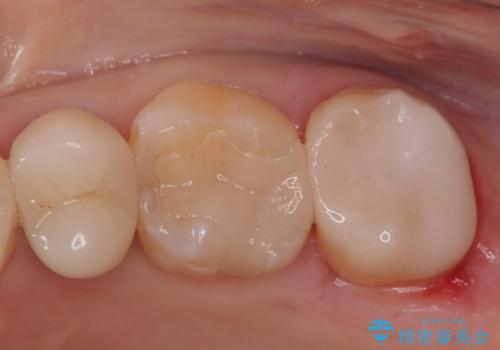

金属のインレーの下と、歯と歯の間も虫歯だったため、つなげた形でセラミックインレーにて修復を行なっています。

e-max プレスインレーを用いることで、適合の良い治療ができます。